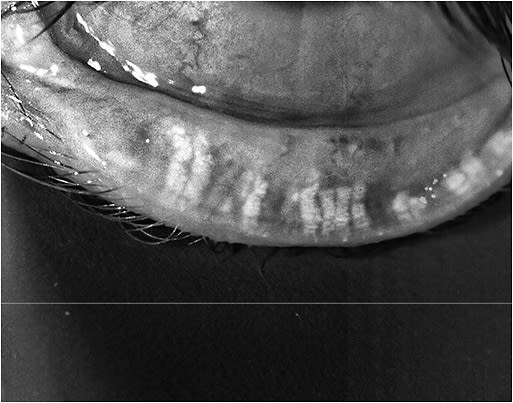

Next, check the ocular surface for dry eye disease (DED). DED has been documented to affect the preoperative measurements, or biometry, used to determine the proper IOL power. Specifically, research shows that biometry can be off by as much as 2.00 D in both sphere and cylinder, secondary to an unstable tear film; resulting in the insertion of the incorrect power. Secondly, an unstable tear film can be the cause for discomfort post-operatively, increased risk of infection and inflammation, as well as a root of fluctuating vision. Thus, a healthy ocular surface is an integral part of a successful surgery. (For information on diagnosing DED, see https://bit.ly/2MgiJYe .) If the patient has DED, it is your, the referring optometrist’s, responsibility to properly treat the patient and ensure all is stable before referring them to the surgery center. (For information on the latest DED treatments, see https://bit.ly/2JED7Nz .)